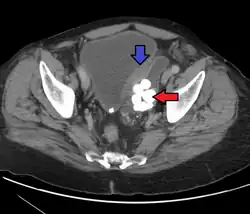

Diverticulum of the urinary bladder of a 59-year-old man, transverse plane -

Bladder diverticula containing stones: the bladder wall is thickened due to possible transitional cell carcinoma. -